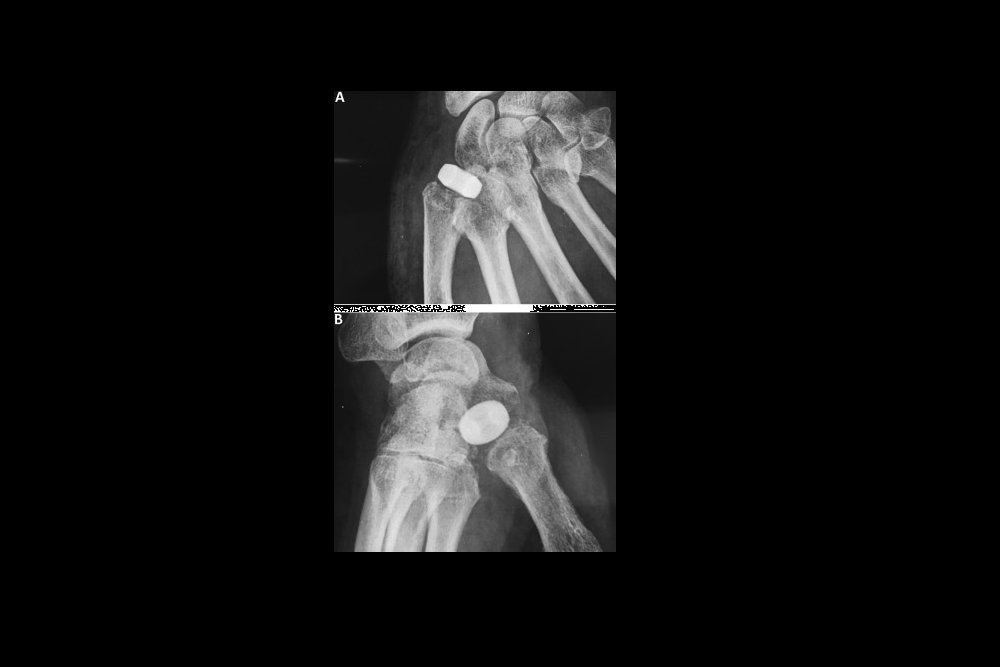

Ensemble Orthopedics Inc. today announced that it has received 510(k) clearance from the U.S. Food and Drug Administration for its Ensemble CMC Implant. The Ensemble CMC was designed to treat patients with early-stage osteoarthritis of the carpometacarpal (CMC) joint using…